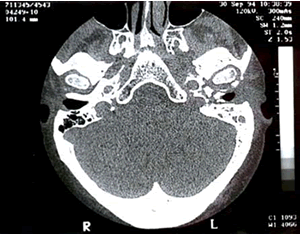

Estudios de imagen:

TC

Erosión del hueso cortical y anormalidades de los tejidos blandos hasta el hueso temporal y a lo largo de la base del cráneo.